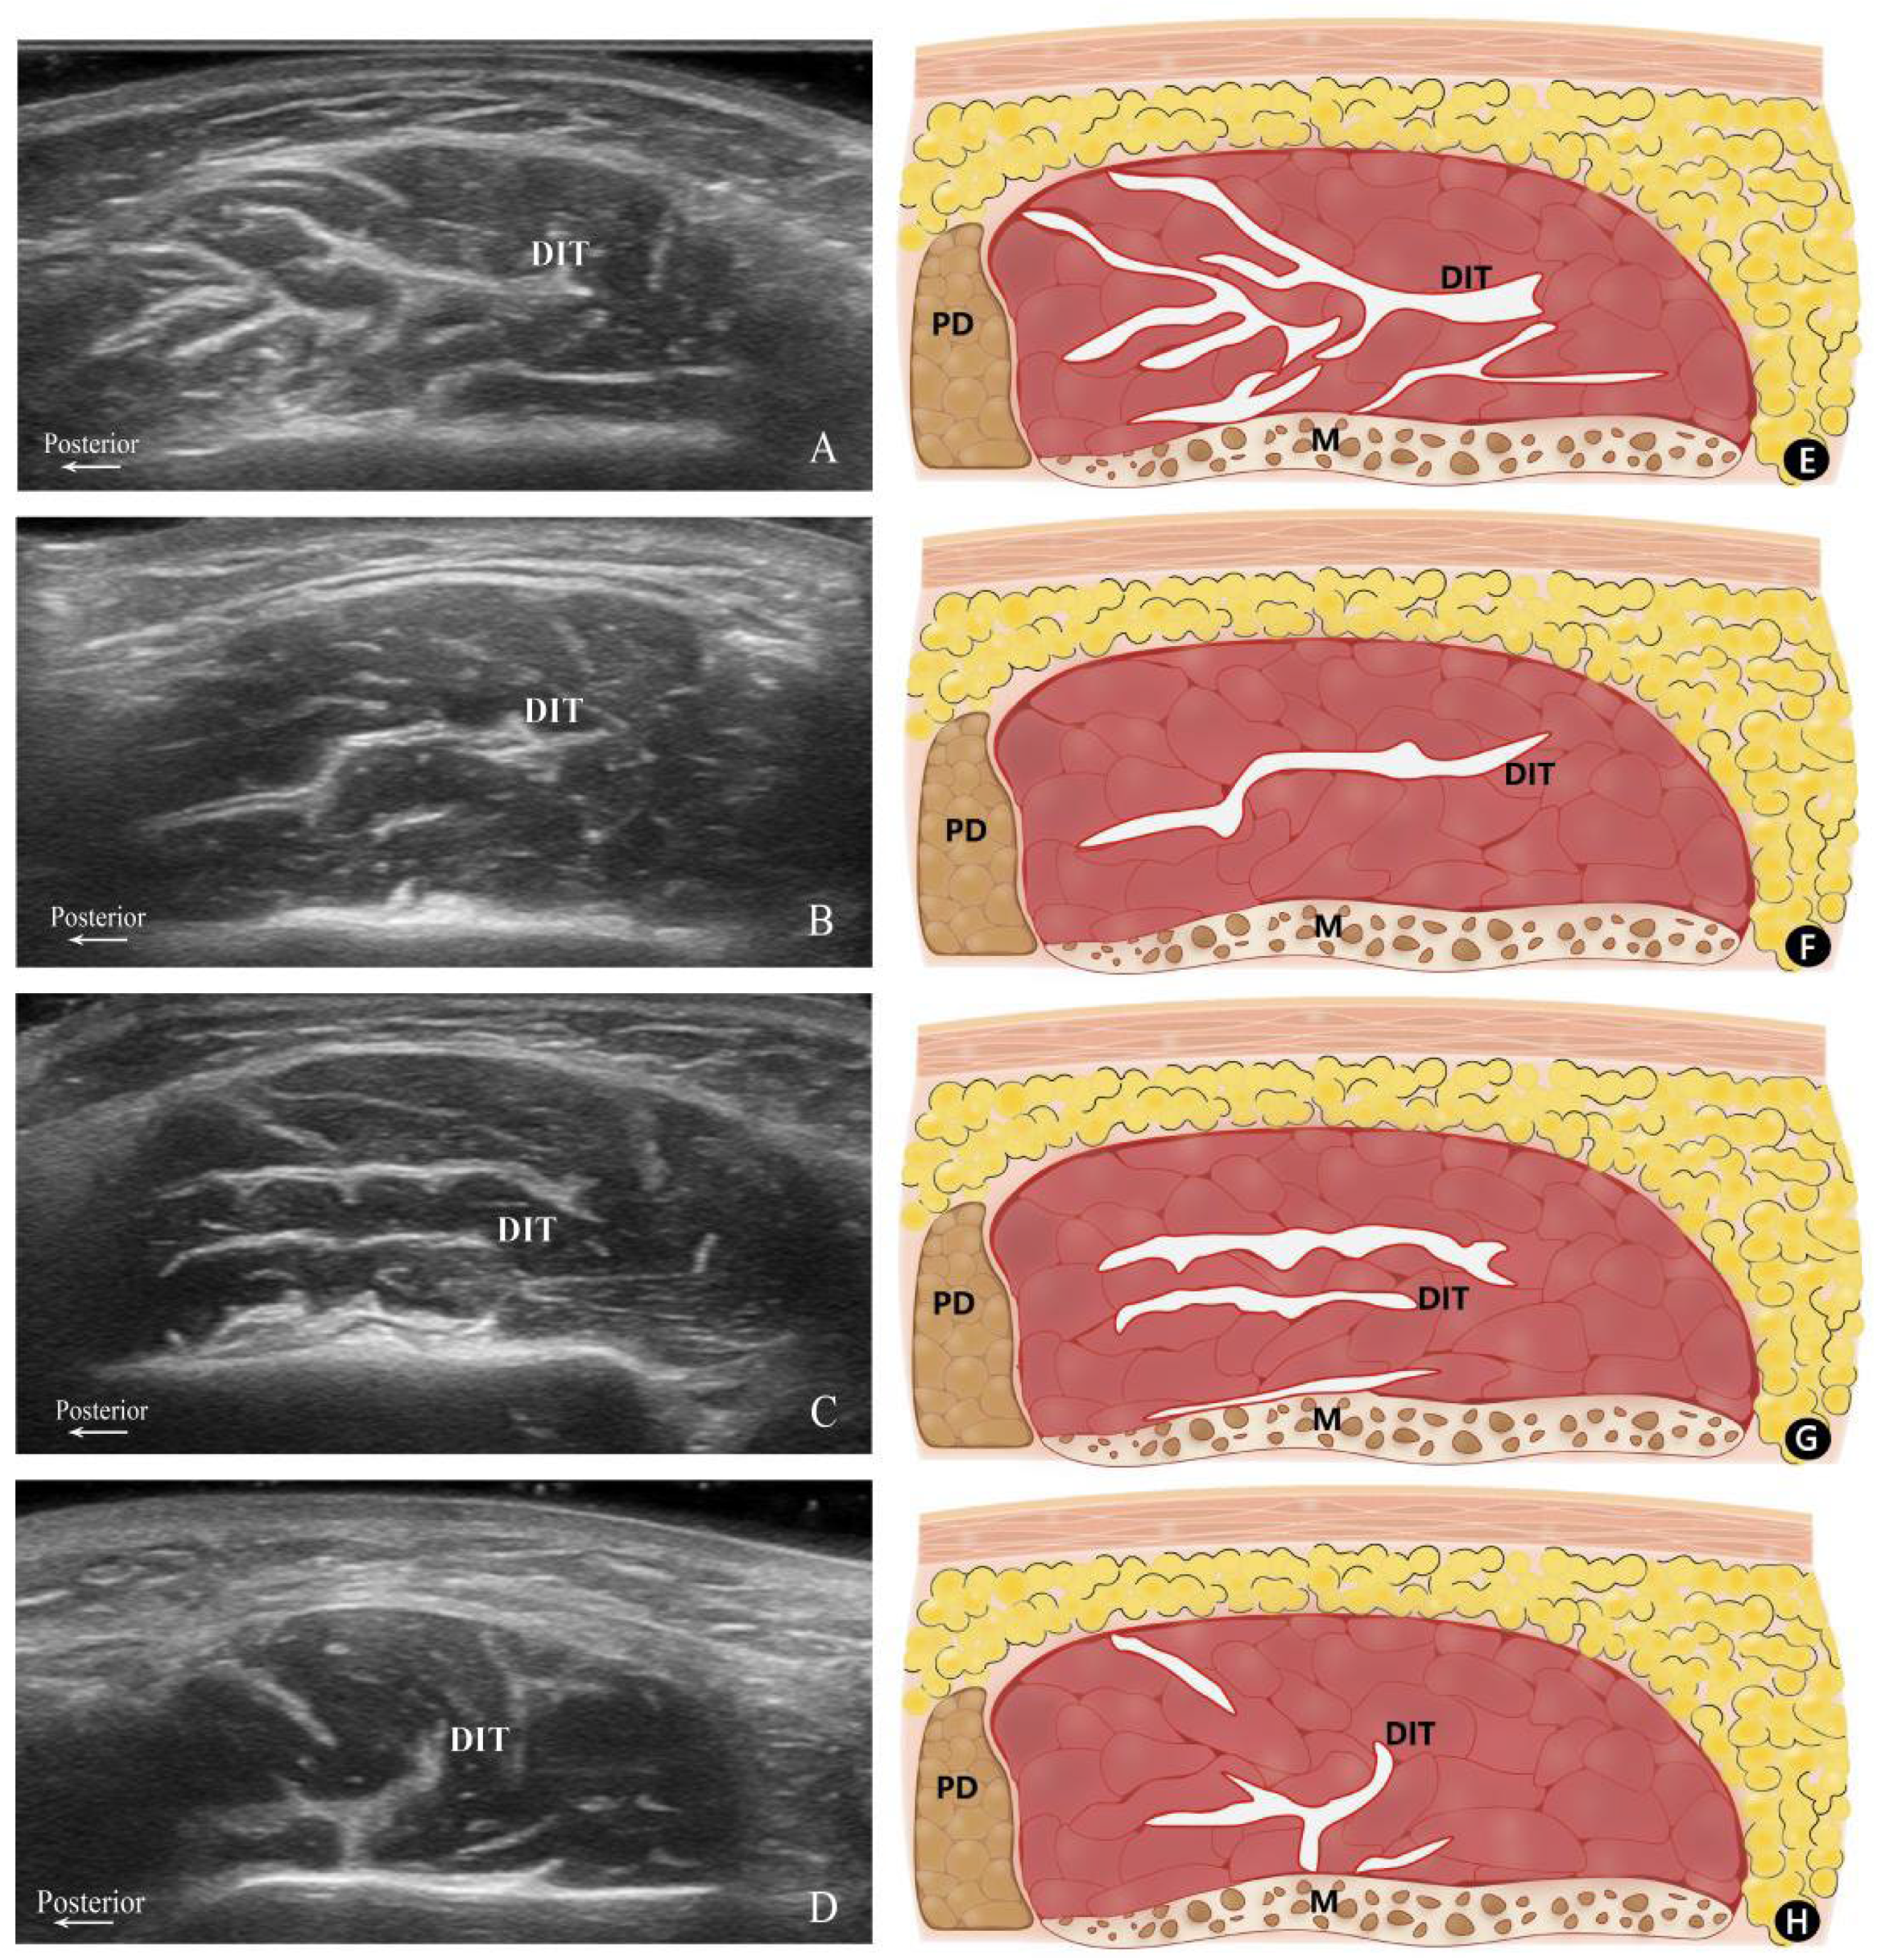

2.2. Classification of DIT Patterns